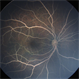

- Lipemia Retinalis

- Lipemia-OS.